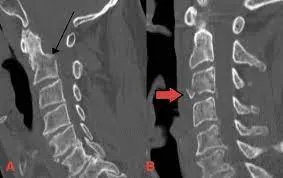

3. Cervical Spine Fractures: Concepts, Imaging & Clinical Insights By Dr. Jitesh Manghwani

This lecture will change the way you approach cervical spine injuries.

Key Highlights:

🔹 CVJ anatomy: Occiput–Atlas–Axis made easy

🔹 Key fracture patterns in young vs elderly patients

🔹 Diagnosing vertebral artery injury

🔹 High-yield takeaways on CT/MRI usage

🔹 Real-life case examples + exam-ready nuggets

Click Here to Watch the Video →